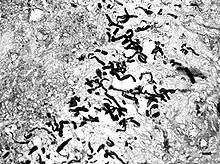

It is suspected that pythiosis is caused by invasion of the organism into wounds, either in the skin or in the gastrointestinal tract.[2] The disease grows slowly in the stomach and small intestine, eventually forming large lumps of granulation tissue. It can also invade surrounding lymph nodes. Symptoms include vomiting, diarrhea, depression, weight loss, and a mass in the abdomen. Pythiosis of the skin in dogs is very rare, and appears as ulcerated lumps. Primary infection can also occur in the bones and lungs.

In horses, subcutaneous pythiosis is the most common form and infection occurs through a wound while standing in water containing the pathogen.[3] The disease is also known as leeches, swamp cancer, and bursatti. Lesions are most commonly found on the lower limbs, abdomen, chest, and genitals. They are granulomatous and itchy, and may be ulcerated or fistulated. The lesions often contain yellow, firm masses of dead tissue known as kunkers.[4] It is possible with chronic infection for the disease to spread to underlying bone.[5]